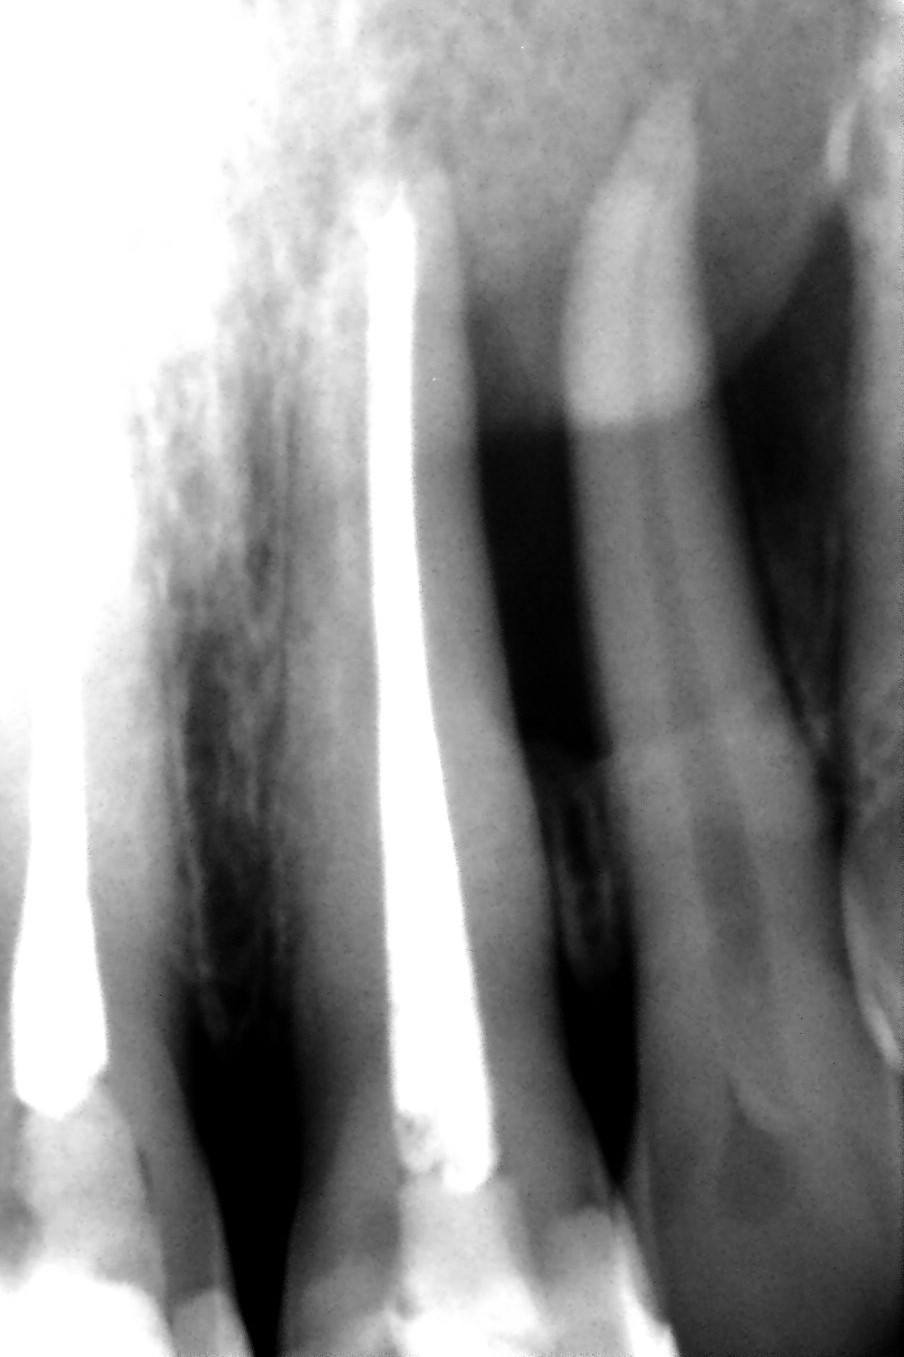

In 2006 wordt P. naar onze praktijk verwezen wegens een laesie in de bovenkaak, regio 21, 22, en 23. De laesie van (waarschijnlijk) endodontische origine, een LEO, zo treffend door professor Herbert Schilder benoemd, heeft een vorm op de röntgenopname die afwijkend genoemd mag worden.

De laesie gaat niet uit van de apices van elementen 21 en 22. De apices lijken nog door bot omgeven. Terwijl je zou verwachten dat, indien er sprake is van een endodontische oorzaak, de laesie zeker de wortelpunten van de betreffende elementen zou omvatten. En dat is hier niet zo.

Afgaande op de röntgenfoto’s zou verondersteld kunnen worden dat er een fractuur zit in element 21 of 22. Een fractuur halverwege een van de wortels zou tot een laesie met deze vorm kunnen leiden.

Of element 22 is avitaal en er is een lateraal kanaal halverwege de radix waaromheen de laesie zich gevormd heeft.

Of er is een ongevuld en niet gereinigd lateraal kanaal in element 21.

Op basis van de beginfoto uit 2010 durven we de stelling wel aan dat er een lateraal kanaal in het spel moet zijn. het zwaartepunt van de laesie zit duidelijk niet bij de apex van de 22, maar halverwege de radix. Op de eindfoto’s uit 2018 zien we er aanwijzingen voor. Maar soms zijn laterale kanalen zo smal dat het beetje sealer en gutta dat erin zit niet te zien is op röntgenfoto’s.